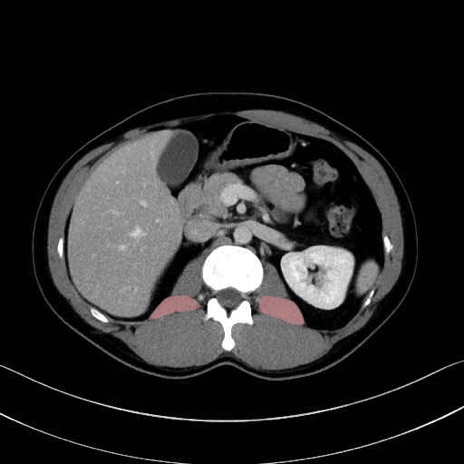

2. 腸腰筋群と骨盤底筋

大腰筋 (Psoas major)

腸骨筋 (Iliacus)